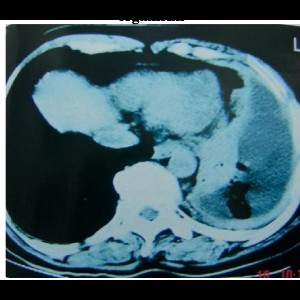

Transcatheter Intervention for Infantile Hepatic Hemangioendothelioma with Amplatzer Duct Occluder II

Transcatheter Intervention for Infantile Hepatic Hemangioendothelioma with Amplatzer Duct Occluder II

READ MORE

Transcatheter Intervention for Infantile Hepatic Hemangioendothelioma with Amplatzer Duct Occluder II

Transcatheter Intervention for Infantile Hepatic Hemangioendothelioma with Amplatzer Duct Occluder II

READ MORE